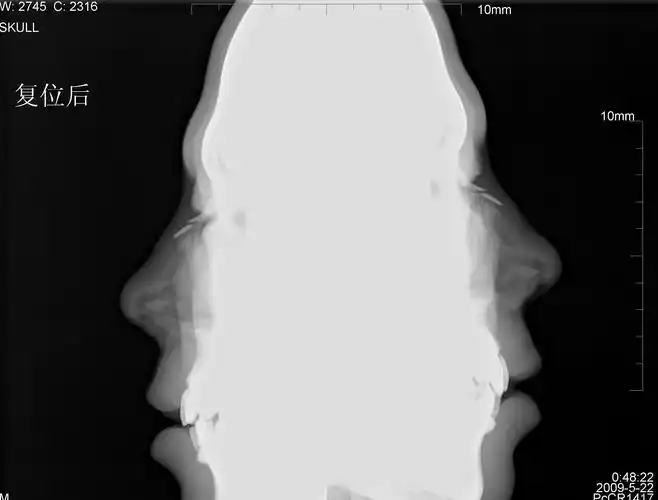

照ct说我鼻中隔多处骨折,骨折碎片向内凹陷.我想问下

薄膜x 射线侧鼻骨 (颅侧面观),在右侧的空白区域

ct51740:鼻骨ct,请会诊!

鼻中隔骨折诊断临床x线初查hrct可靠鉴别诊断鼻缝鼻骨

清晰图讲解鼻骨骨折影像学诊断